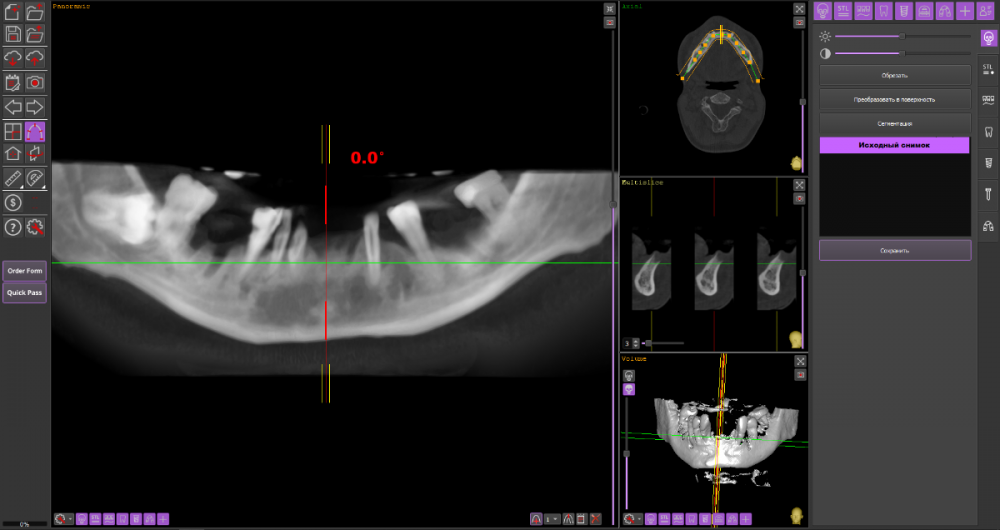

Сергей34 Опубликовано 19 октября, 2022 Поделиться Опубликовано 19 октября, 2022 Приветствую господа и дамы. Значит картина следующая, мне 34 года и обладаю пародонтитом. Нижних зубов уже почти лишился осталось по краям 6 зубов которые прилично шатаются. (несколько месяцев ношу протез квадротти частичный). Верхние зубы 12 шт пока стоят (их буду шинировать, кюретаж все дела), этих манипулаций хватит ещё года на 2-5 может - как повезёт. На верхней челюсти по кости всё очень печально, на верху по бокам без синус лифтинга вообще не поставить импланты. (а синус лифтинг и основательную неопределенность результата я не вывезу по финансам и здоровью). Принял решение ставить вниз импланты, есть возможность поставить 4 или 6 имплантов. А в перспективе через 3-5 лет уже когда верхние зубы начнут выпадать поставить на верх 4 импланта что получится поставить. ------------------- Так вот в чём мой вопрос, какую конструкцию будет правильнее поставить сейчас внизу на 4/6 имплантов, чтобы в будущем когда буду протезировать верх эти 2 материала друг друга не разбили. Врач мне сказал что наверху без синус лифтинга можно сделать только сьёмный протез на 4 имплантах. Подскажите пожалуйста какое протезирование сейчас будет оптимально выбрать на низ и как это выглядит, если не сложно приложите пожалуйста фото этого решения. Спасибо. Ссылка на комментарий

Сергей34 Опубликовано 24 октября, 2022 Автор Поделиться Опубликовано 24 октября, 2022 (изменено) 1 час назад, Bier сказал: я бы ставил 6/6 условия позволяют. Ждать особого смысла нет. спасибо. врач что смотрел кт - сказал что в задних частях возможности установить нет без подскадки кости. Впереди точно получится поставить 6 или нет, сможет сказать только после удаления зубов и спустя месяц когда заживёт. Не знаю можно ли ему доверять. Изменено 24 октября, 2022 пользователем Сергей34 Ссылка на комментарий